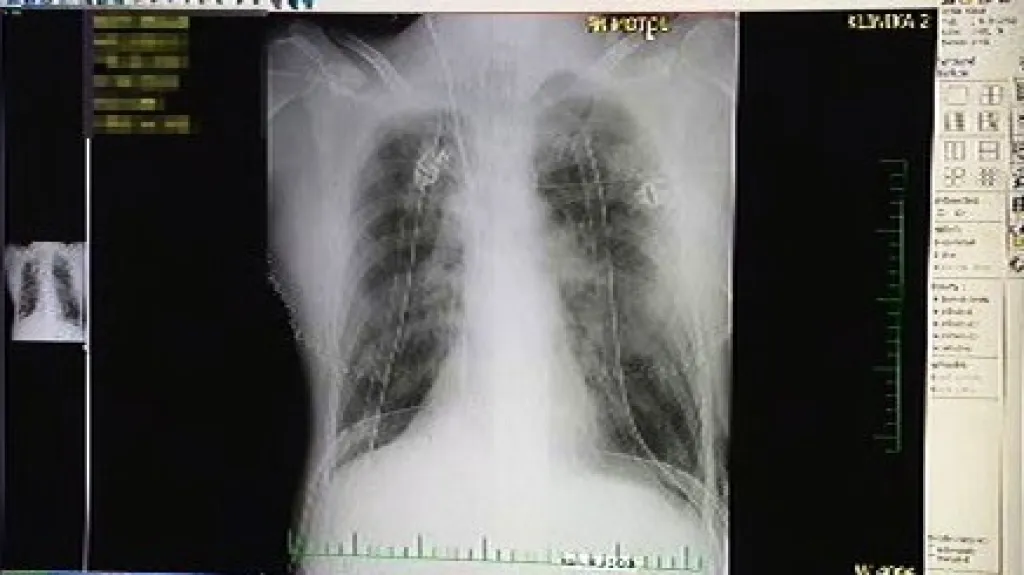

Praha - Po třináctileté praxi transplantací plic v Česku stále není vyřešeno, jak mají pojišťovny operace hradit. Lékaři je proto musejí fakturovat na jednotlivé úkony a nemocnice na tom tratí. Přitom v zahraničí transplantace znamenají pro nemocnice zisky. Transplantace plic v Česku zatím kontinuálně provádí jen pražská FN Motol. Ještě před několika lety na jednu operaci dostával dva miliony korun, tedy částku, která zahrnula operaci, následnou péči, potřebné léky i náklady na případné komplikace.

Na čekací listině pro transplantaci je momentálně 50 lidí. Podle lékařů by nové plíce ale potřeboval minimálně dvojnásobek pacientů. Transplantace plic se v Česku dělají od roku 1997. Od té doby jich lékaři provedli již 149.